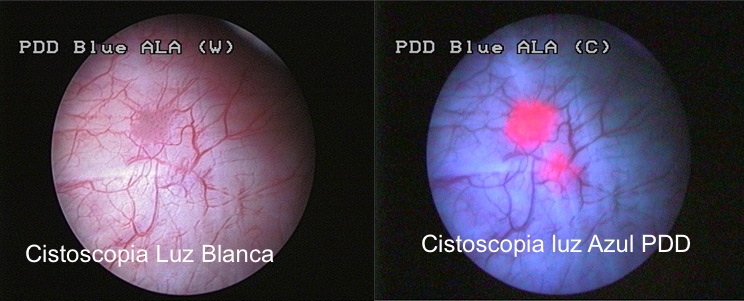

Si se sospecha de la existencia de un tumor, es necesario realizar una exploración denominada cistoscopia, en la que el urólogo observa el interior de la vejiga a través de la uretra, con un instrumento denominado cistoscopio.

Hoy día existen modernos instrumentos flexibles que permiten realizar esta exploración de forma indolora, incluso sin necesidad de anestesia.